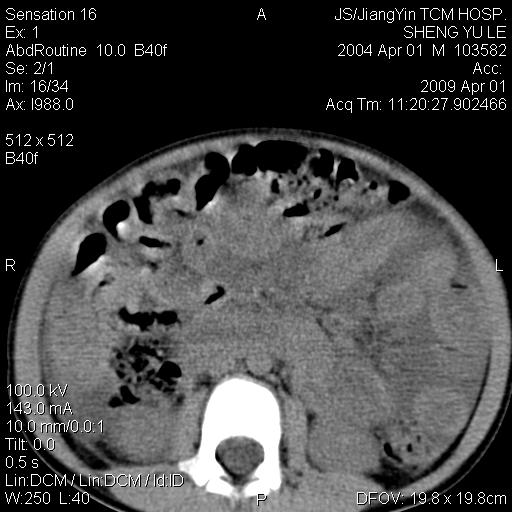

m,5岁。尿痛尿频数天。既往无病史。ct平扫腹盆腔积液。膀胱壁明显增厚。另可见心包增厚。wbc5万,骨髓穿等结果。请指教。

膀胱影像表现结合临床应该是急性膀胱炎症,但为什么有腹水呢?双肾输尿管无扩张,泌尿系压力应该不大不至于引起尿外渗,应该是腹膜感染引起的,但楼主没有提及相关症状,腹膜及膀胱结核?患者白细胞5万(结核不至于这么高啊),脾脏增大,是不是有白血病?进一步检查。。

腹水,膀胱壁增厚,wbc5万,结合临床,支持感染性疾病---感染性腹膜炎、腹水,急性膀胱炎,败血症。期待结果。